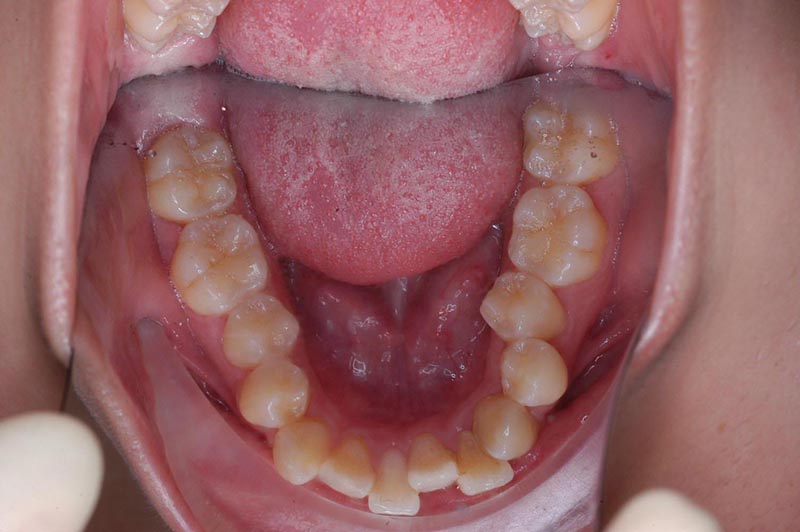

初診時

主訴 口が閉じづらい 診断名 アングルⅠ級上下顎前突症例

初診時年齢 19歳5ヵ月 性別 動的治療期間 26ヵ月

口腔内所見 大臼歯関係はⅠ級。顔面正中に対して上顎正中は一致しており、下顎正中は右側に偏位していた。上下顎前歯は大きく唇側傾斜し、overjetが7.8mmの上突咬合、両突歯列、叢生歯列弓であった。